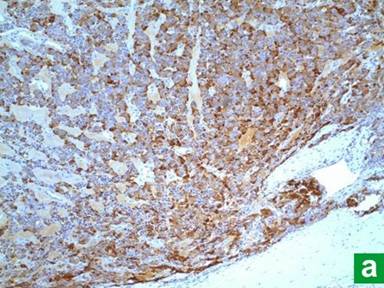

A 64-year-old woman was admitted to our hospital in 2000 for evaluation of severe epigastric pain, chronic diarrhea and a 11.5 kg weight loss over last few years. Past medical and family history were unrevealing for any endocrine tumors. Esophagogastroduodenoscopy showed severe duodenitis and an atypical post-bulbar ulcer. Because of the classic presentation, atypical peptic ulcer disease and chronic diarrhea with weight loss, we pursued a work-up for Zollinger-Ellison syndrome. Her serum gastrin level was elevated (198 pg/mL; reference range: 0-42 pg/mL). CT scan of the abdomen and endoscopic retrograde cholangiopancreatography showed a 3 cm mass in the head of the pancreas compressing the main pancreatic duct. Subsequent octreotide scan revealed an octreotide positive mass in head of the pancreas suggestive of a neuroendocrine tumor. Serum insulin, glucagon, somatostatin and vasointestinal polypeptide (VIP) levels were within normal range. She underwent a Whipple procedure in 2000 with resection of the mass that proved to be a 2.8 cm gastrinoma with focal venous and perineural invasion (Figure 1). All resected lymph nodes were negative on H&E and immunostaining (Figure 2). Immunohistochemically, tumor cells were diffusely positive for gastrin, and focally positive for chromogranin-A, synaptophysin and insulin (Figure 3). Tumor cells were negative for glucagon, VIP or somatostatin. Post-operatively, follow-up serum gastrin level was suppressed (18 pg/mL). She received no adjuvant chemotherapy or radiotherapy.

Figure 3. Immunohistochemistry demonstrates diffusely positive staining for gastrin (a.), and focally positive for insulin (b.). |